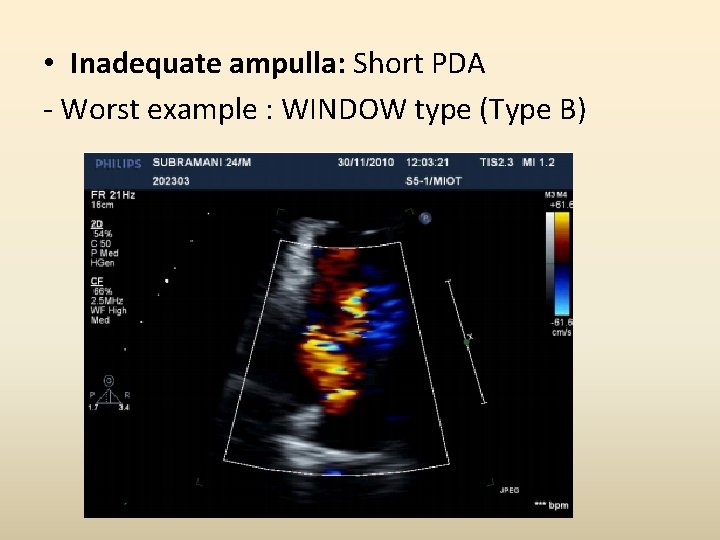

• Inadequate ampulla: Short PDA - Worst example : WINDOW type (Type B)